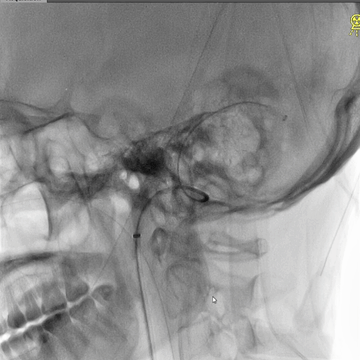

右侧股动脉穿刺置5F鞘,股动脉造影路图下穿刺右侧股静脉,置入8F鞘。6F长鞘(90cm,Cook)+6F中间管(115cm)+4F多功能管(125cm)组成同轴,泥鳅导丝导引下进入右侧颈内静脉颅底位置。泥鳅导丝超选进入右侧乙状窦和横窦,4F多功能管跟进乙状窦一段距离后难以继续前进,此时6F中间管在内衬4F管支撑下进入乙状窦,并前推进入横窦,成功建立治疗通道。

微导丝(Command 14)微导管配合,进入上矢状窦中部,交换出微导管,保留微导丝作为参照,引导后续微导丝微导管超选直窦。

微导管微导丝(Command 14)超选直窦成功后,交换出微导管。经微导丝送入3*30mm球囊,扩张直窦近段,并以BAT技术将6F中间管推送入直窦内,行血栓抽吸操作,吸出多量红色血栓。